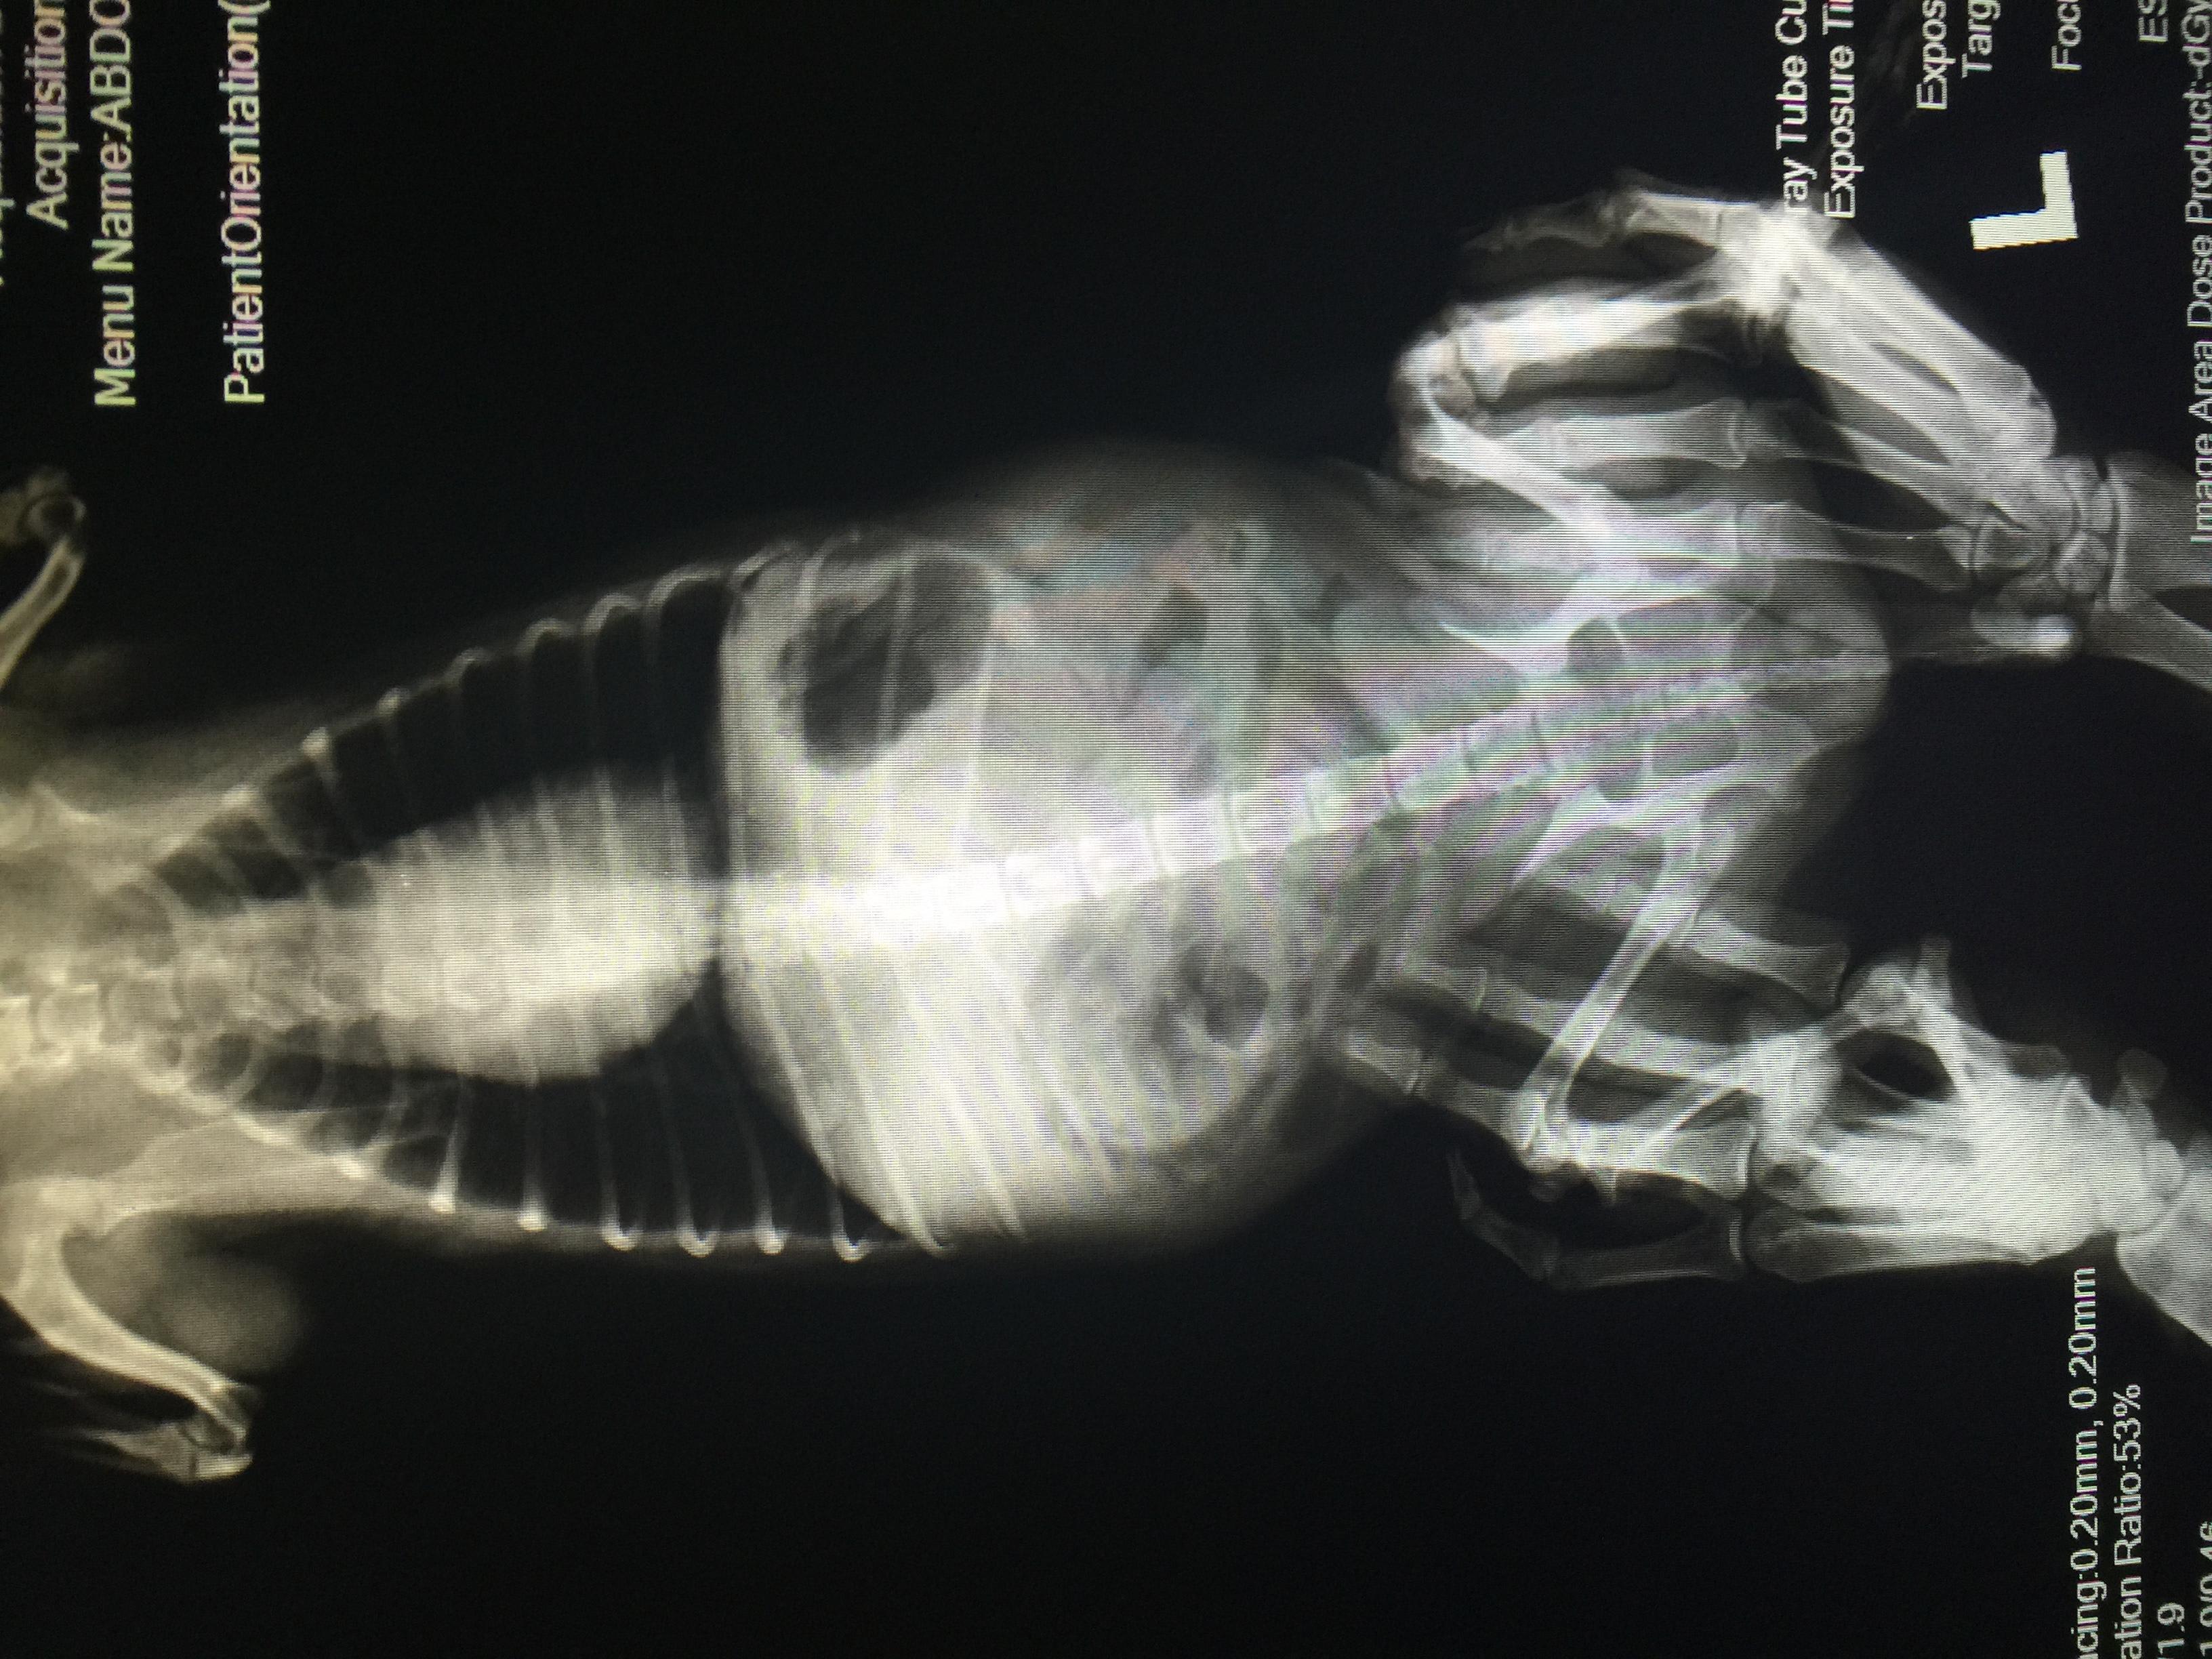

First of, thanks so much to Dr. Roca for the detailed response on my first post! I didnt include my dog's xray pics (taken today) so i'm attaching it here. Still waiting to hear back from my vet but would like to know if there are any red flags or possible issues i should discuss with her. Maicah is 10-12yo, shipoo mix, currently on ehrlichia meds: doxy and prednisone. Her gait is a bit stiff and i saw slight signs of discomfort when i massage her back. Any info will be much appreciated!

The x-rays are a bit difficult to interpret because they are a little fuzzy, but I can see that Maicah has some minor changes on the bottoms of her vertebrae - called spondylosis. This can definitely cause discomfort in the back. I would talk to her vet about treatments that can help with this kind of pain. I am not able to evaluate her hind limbs because the assistant's hands are covering them up. Another possible cause of her stiffness is joint pain caused by the ehrlichia infection. This should improve with appropriate treatment.